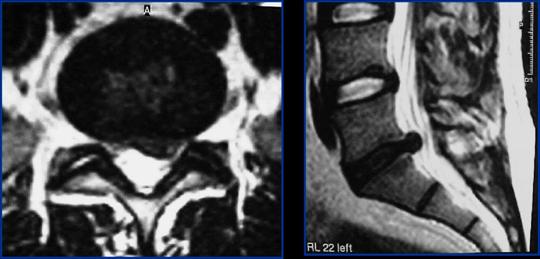

1.- Paciente de 50 años, con HNP L5 – S1, que no respondió a tratamiento conservador, incluyendo antiinflamatorios, fisioterapia y kinesioterapia, por 8 semanas, incluyendo un corticoide peridural por lo que se decidió realizar Nucleotomía Percutánea Automatizada más Apoyo Artroscópico (lo que permite retirar mayor cantidad del tejido herniado).

En este caso se logró una remisión completa del dolor y volvió a trabajar a los 12 días.

2.- Paciente de 45 años, con HNP L5 – S1 derecha que no respondió a tratamiento conservador, por 6 semanas, se realizó Nucleotomía Percutánea Automatizada con Apoyo Artroscópico, con lo que se resolvió el problema y volvió a trabajar a los 10 días.